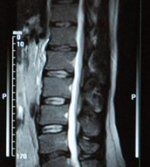

МРТ позвоночника

Магнитно-резонансная томография (МРТ) – наиболее эффективный и точный метод диагностики заболеваний ОДА. С его помощью можно исследовать состояние позвоночника и прилегающих тканей, получить достоверные изображения спинного и головного мозга.

По итогам МРТ-исследования лечащий врач получает серию срезов, позволяющих оценить состояние отделов позвоночника. С помощью МРТ можно визуализировать спинной мозг, тела позвонков, межпозвонковые диски, суставы и нервные корешки.